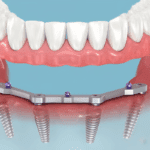

Os implantes dentários são uma solução para quem perdeu dentes. Eles são usados para substituir dentes perdidos ou danificados. Essa tecnologia ajuda muitas pessoas, de jovens a idosos.

Os implantes dentários são muito versáteis. Eles podem ser usados para um dente, vários dentes ou até a boca toda. Isso ajuda muitas pessoas que perderam dentes.

| Versatilidade | Podem substituir desde um único dente até toda a arcada dentária |